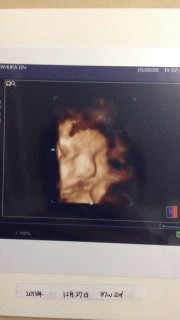

推定体重2900gの元気な男の子です。 いつ産まれるかドキドキの毎日、 昨日の健診では、何だか悩んでるみたいだね、って先生に言われました(笑) 今までのエコーを見ると私の父に似てると思ってたけど、なんだか旦那にも似てる気がしてきました。

ぶにゅーって潰れた顔してます(笑)産まれた今でもこの顔する!